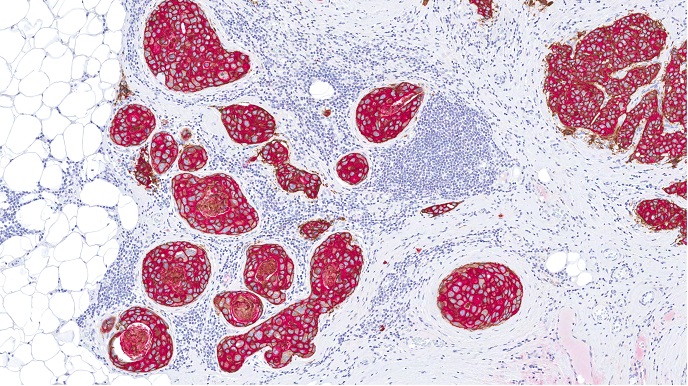

El destino de una célula se encuentra en manos de los DR, ya sea mediante la interacción de éstos con un ligando (lo que propicia la supervivencia) o, en ausencia de un ligando, a través de la inducción de la muerte celular programada o apoptosis. Por ello, no resulta sorprendente que exista un vínculo entre la función de supervivencia y muchos tipos de cáncer y que, por consiguiente, los DR se hayan convertido en un objetivo para las estrategias terapéuticas. Conseguir que las células elijan la vía de la apoptosis a través de un DR parece pues una buena manera de eliminar el cáncer. Los socios del proyecto financiado por la Unión Europea NOTCH3DR («Investigación de un nuevo papel de la Notch3 como receptor de dependencia y su importancia en vivo») investigaron el DR recientemente descubierto Notch3. Los socios del proyecto descubrieron que la sobreexpresión de la Notch3 inducía la apoptosis en una amplia gama de células cancerosas. Cultivando células cancerosas que expresan Notch3 junto con células que expresan ligandos, los investigadores obtuvieron pruebas de la naturaleza dual de Notch3, ya que en este caso no se producía la muerte celular. Desde el punto de vista molecular, el equipo demostró que sí se producía la muerte celular en presencia de caspasas, un grupo de enzimas implicadas en las vías de la apoptosis. Es más, la caspasa-9 era absolutamente necesaria para la apoptosis inducida por Notch3. La relación parece ser que las caspasas provocan la escisión de la Notch3 durante el proceso de inducción; los investigadores intentarán ahora poner a prueba esta hipótesis utilizando mutantes que tengan inactivadas las caspasas responsables de la escisión. Para estudiar la participación de la Notch3 en el cáncer, los miembros del consorcio analizaron la expresión de los ligandos de la Notch3 en líneas celulares de cáncer de pulmón y de mama y observaron que se daba una importante correlación entre la expresión de Notch3 y la de alguno de sus ligandos. En concreto, encontraron correlaciones entre la expresión de la Notch3 y la de sus ligandos DLL-4 (ligando 4 similar a delta) y Jagged-2 en líneas celulares de cánceres de pulmón y de mama, respectivamente. Por otra parte, también observaron que la expresión de otro ligando de Notch3 denominado Jagged-1 aumentaba significativamente en los pacientes con cáncer renal y, lo que es más importante, que la inhibición de dicho ligando inducía en los cultivos de carcinoma renal la muerte celular programada. Según los miembros del consorcio Notch3dr, el camino a seguir consistiría en inducir la actividad DR de la Notch3 en las células cancerosas mediante agentes que interfieran inhibiendo la interacción de la proteína con sus ligandos. Un enfoque particularmente prometedor se centraría en el desarrollo de agentes específicos para Notch3 que no afectaran a otras proteínas de la misma familia, con lo que se aumentaría su especificidad y se reduciría su toxicidad.